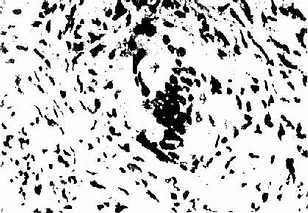

结节病肉芽肿在组织切片上可见为皮样细胞的聚集,其中有多核巨噬细胞,周围有淋巴细胞,而无干酪样病变(图2-11-1)。在巨噬细胞的泡浆中可见有包涵体,如卵圆形的舒曼(Schaumann)小体,双折光的结晶和星状小体(asteroid body)(图2-11-2)。肺结节病的初发病变有较广泛的单核细胞、巨噬细胞、淋巴细胞浸润的肺泡炎,累及肺泡壁和间质。肺泡炎和肉芽肿都可能自行消散。但在慢性阶段,肉芽肿周围的纤维母细胞胶原化和玻璃样,成为非特异性的纤维化。肉芽肿的组织形态学表现并无特性,可见于分支杆菌和真菌感染,或为异物或外伤的组织反应,亦可见于铍病、第三期梅毒、淋巴瘤和外源性变态反应性肺泡炎等,应行鉴别。但在多器官中见到同样的组织病变,结合临床资料,可诊断本病。

图2-11-1 结节病肉芽肿

结节主要由类上皮细胞组成,中央无干酪样坏死,周围淋巴细胞少,边界清楚